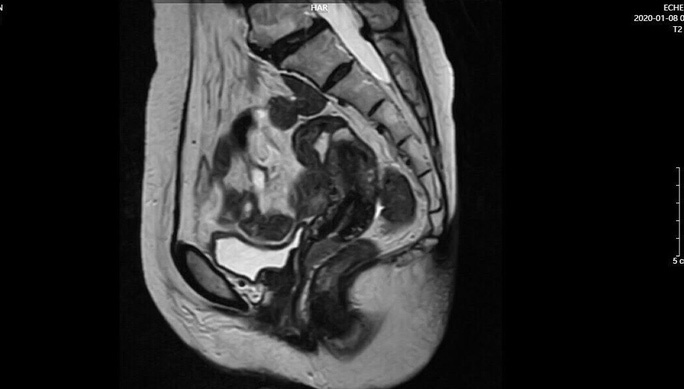

Trước đó, bệnh nhân T. có tình trạng chảy máu âm đạo bất thường sau mãn kinh hơn hai tháng, tuy nhiên vì ngại và chủ quan nên không đi khám. Chỉ đến khi thấy khó chịu nhiều hơn, bệnh nhân mới đến bệnh viện. Tại đây, kết quả chụp cộng hưởng từ và sinh thiết cho thấy bệnh nhân bị ung thư âm đạo giai đoạn sớm.

Hình ảnh chẩn đoán ung thư của nữ bệnh nhân. Ảnh: BSCC.